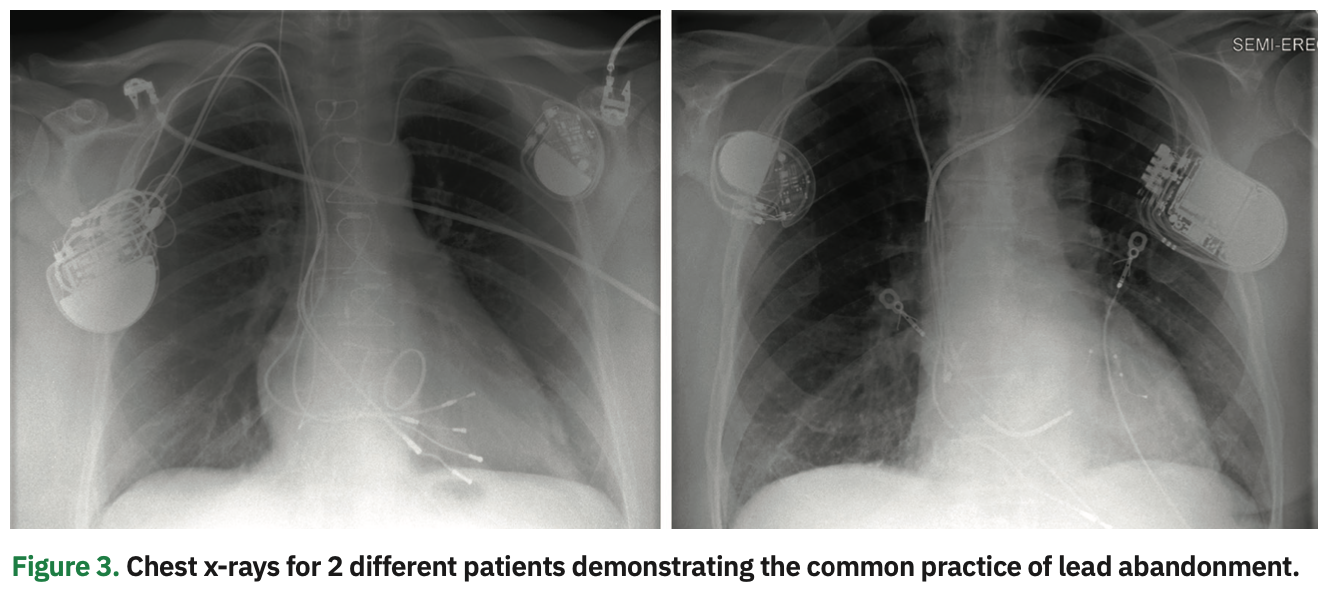

As a consequence, TLE procedures have been considered a category of high-risk interventions, mandating the immediate availability of a multidisciplinary team including a cardiothoracic surgeon, cardiac anesthesiologist, perfusionist, and nursing personnel. This has resulted in increased procedural cost, inefficiency, and resource utilization that are not be feasible at many institutions. The increased procedure complexity has significantly curtailed incorporation of TLE programs beyond a relatively limited number of experienced lead management centers, and hence, there is a limited proliferation of TLE skills among EP trainees. Furthermore, access to care has been hindered for many patients who would benefit from lead extraction for noninfectious indications. Not infrequently, these patients are managed by leaving the nonfunctional leads and adding new leads on the same or contralateral side with no attempt at removing the lead that otherwise could be removed with very minimal added risk. In fact, it is estimated that almost 1 in every 4 patients requiring extraction for CIED infection had a previously abandoned lead in place, a manifestation of the common practice of lead abandonment (Figure 3).3